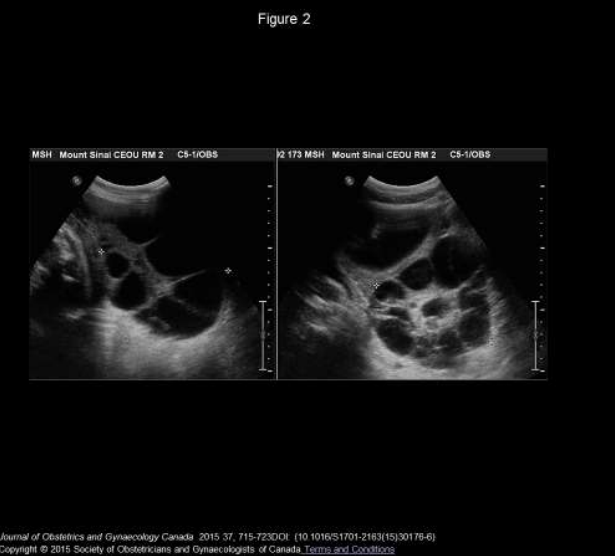

Figure 2

Us: s-ohss/ HL is characterized by large bilateral adnexal masses, many thin-walled small theca lutein cysts, classic appearance of a ‘spoke wheel’, and Ascites can be present. Lack of solid components help to differentiate sohss from ovarian malignancies.